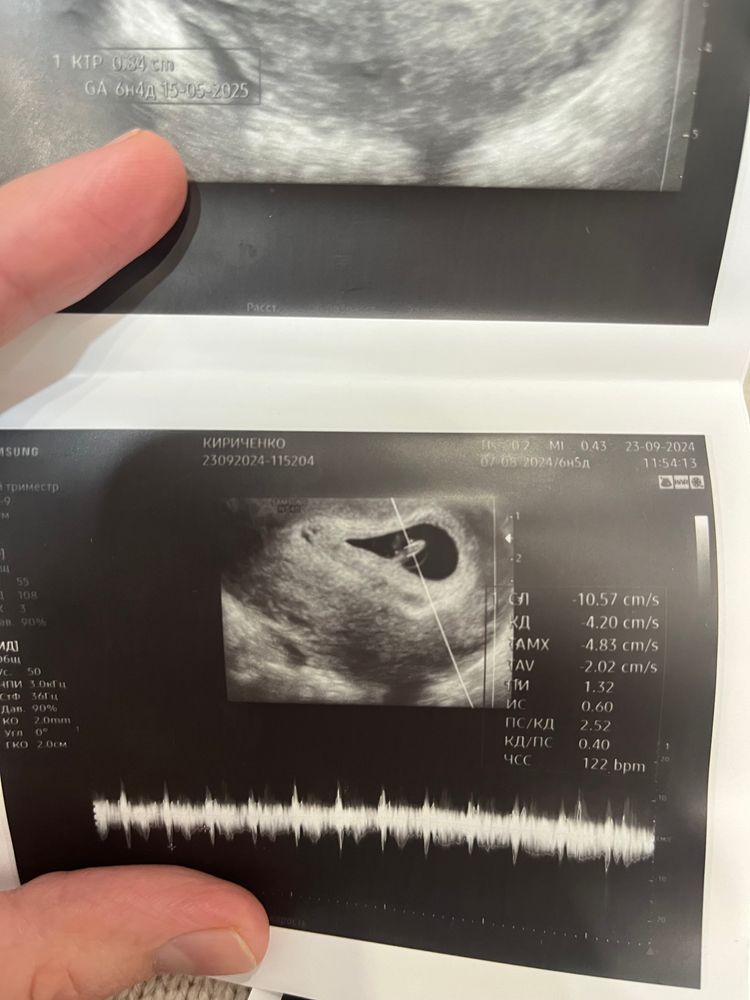

Алена, Нашла😄 Не знаю какой из них подойдет 😅все скинула Изображение Изображение Изображение

Виолетта, у вас не понятно) по середине 🤣

Алена, смотрят же на на эмбрион. У девушки все предельно понятно по методу Рамзи.